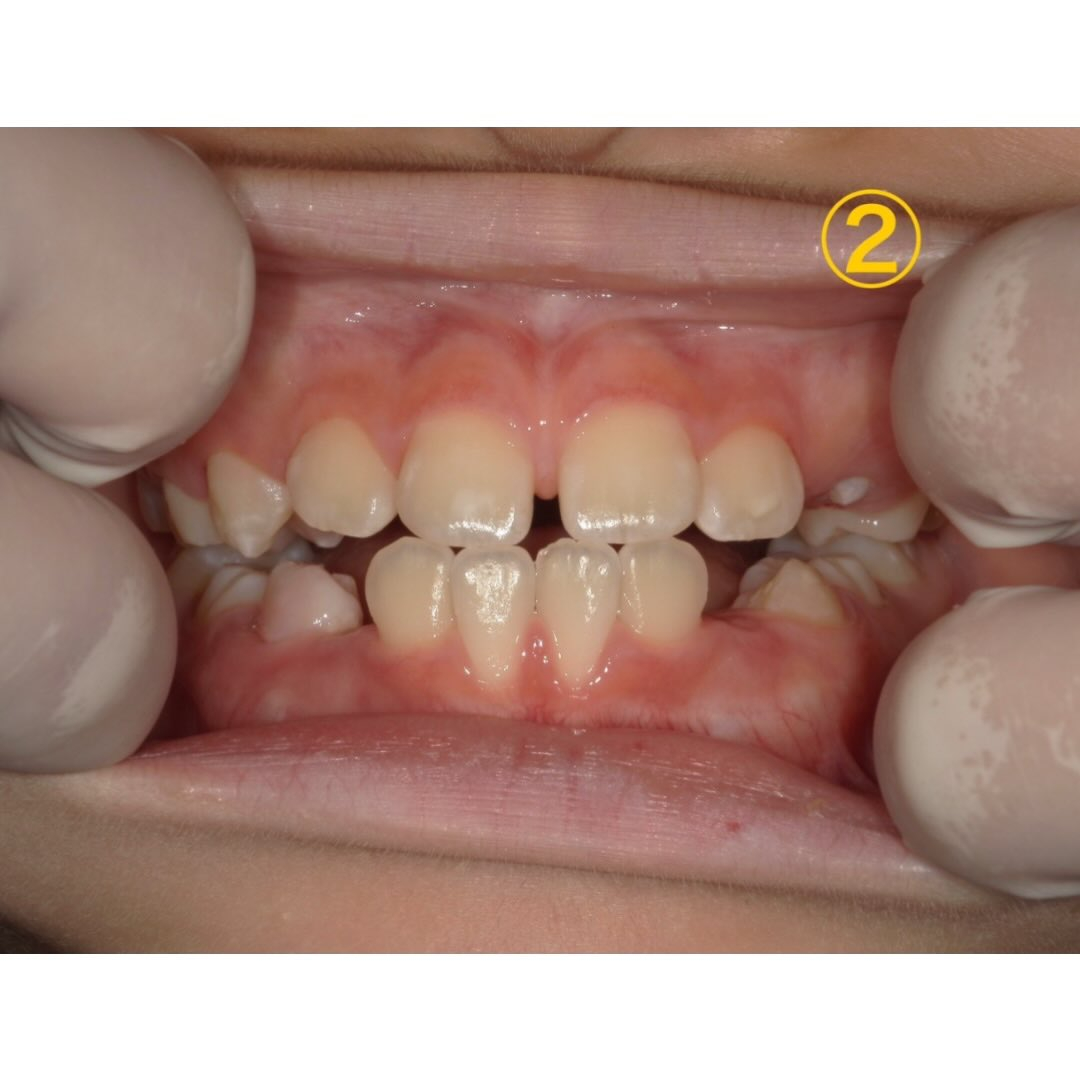

①〜③は1年ごとの1番変化が分かる写真を抜粋しました。

①、②の時は特に目立った汚れもなく生え変わりもあるので3ヶ月に1回定期検診を行っていました。